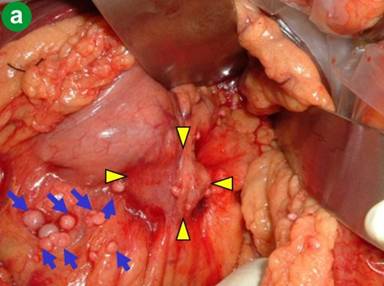

The patient was diagnosed with an intraductal papillary mucinous carcinoma with lymph-node metastasis, and underwent an operation. Laparotomy presented the cystic tumor and white-colored nodules on the surface of the transverse mesocolon (Figure 2a), which was histologically diagnosed as acinar cell carcinoma (Figure 3ab) and deemed unresectable.

Figure 2. a. Findings of the main tumor and the surrounding nodules in the first operation, and (b.) macroscopic appearances of the resected tissues and the transection of the main tumor. |

In the second-look operation, there was no lesion that was deemed unresectable. The disseminations on the transverse mesocolon had disappeared, and the cystic main tumor had shrunk to the induration on the surface of the pancreas with a size of 8x4 mm. This lesion was excised and subjected to histological study, which demonstrated a small nest of cancer cells in the granulation tissue (Figure 3cd), which suggested a grade 2 effect of chemotherapy. Distal pancreatectomy was performed with lymph node dissection as well as ductal adenocarcinoma and resection of the transverse mesocolon (Figure 2b). There was no other microscopic finding except for remarkable infiltration of macrophages into the lymph node. Immunohistochemically, the tumor cells were positive for trypsin, lipase, and chymotrypsin, which are specific for acinar cell carcinoma.